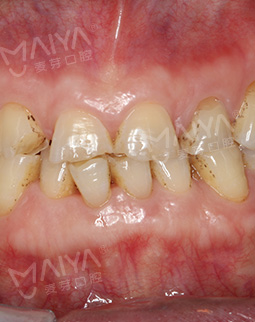

过去的困扰

我是一名老军嫂,跟随部队来深圳37年。早年在深圳市二院看牙齿的时候认识了郑院长,郑院长弄的牙齿到现在都完完整整。前不久吃饭,被鸡肉的骨头磕断了一颗前牙,牙齿断了一半,闭合不上了,食物也咬不了了,吃饭尽量用另一侧咬,我知道牙齿的重要性,一颗牙不管可能就会伤害到全口牙的健康,我去过其他的地方也做过检查,发现牙根已经不能保留了,只能拔牙种牙。

郑院长带领的医师团队,给我讲片子很清楚,说我的左上2牙齿出现松动,但是牙龈状况良好,可以告诉我牙齿即拔即种,无需等待3个月拔牙愈合期,避免二次创伤性伤口,他们以修复为导向,尤其我这种前牙的,还要兼顾咀嚼的咬合功能与美观性,虽然不太懂这个技术,但我还是很信赖郑院长的团队的,也感叹现在技术的先进。方案定制完成后,3D口扫取模,就跟牙刷大小一样的东西在口内扫一下,为了制定导板,种牙的时候更方便。